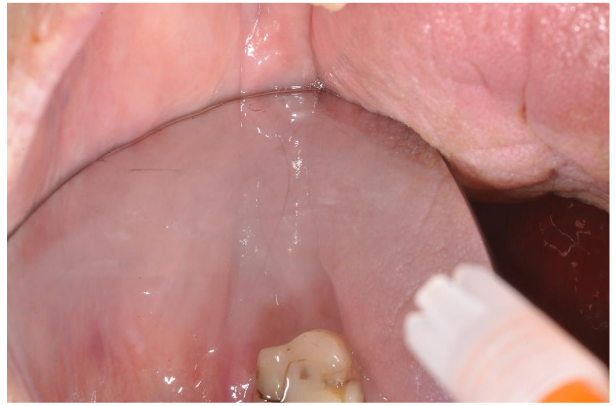

The post-surgery pharmacological protocol included a broad-spectrum antibiotic coverage (amoxicillin cps 1 gr x 3 times a day for 8 days from the day before surgery), accompanied by rinsing with 0.2% chlorhexidine-based mouthwash (1 minute for 3 times a day until stitches removal for 12-14 days). To control the inflammation, corticosteroid drugs for three days (deltacortene cps 5 mg) and granular ibuprofen 600 mg 2-3 times daily as needed was prescribed. The patient had acute pain and swelling for 4 days, well controlled by the anti-inflammatory drugs. The sutures were removed after 14 days and one month later the wound appeared in good conditions, instead the healing was not complete and the gingival flaps were divided by a defect. Anyway, the pain was completely solved (both localized or irradiate to the right ear), no bleeding and no infections into the gingival socket. After 4 months the gingival defect healed completely without any other drug or surgical therapy (image 9).